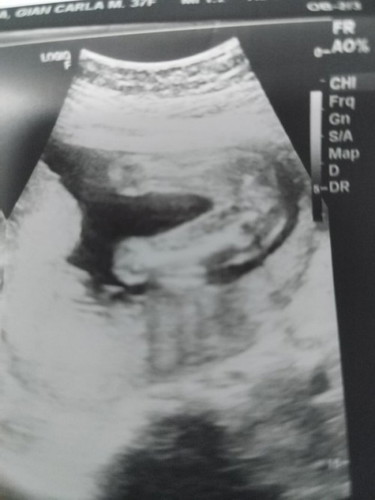

mga mi ask ko lang kung ano gender ni baby? base kasi sa ultrasound ko 70% lang n girl sya. 21 weeks

yan po legs nya s picture.. ano po gender nya?

Parang girl. If legs yan, tingnan mo yung gitna may guhit. Baka po girl.